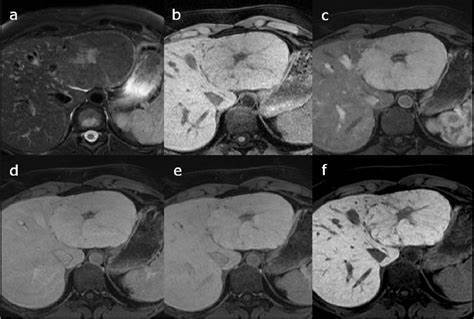

Adenoma hepatico

prolifereção begnica dos hepatócitos com perda de funcionalidade dos mesmos e que apresenta importante influência do uso de contraceptivos e suplementação hormonal com anabolizantes

possui risco de maglinização, principalmente quando > 5cm ou presença de mutação betacatenina

TC: lesão heterogênea, hipervascularizada, geralmente com conteúdo gorduroso no seu interior.

RNM com contraste hepatoespecífico (primovist): padrão ouro

tecido nao funcionante (ausencia de cel de kupffer) nao capta o contraste

Composto por hepatócitos atípicos, mas sem displasia, disposto em placas espessas, com conteúdo variável de glicogênio e lipídeos.

1) HNF1alfa mutado/esteatótico: associado a esteatose hepática, tipicamente indolente e de baixo risco e complicações. Histologia: esteatose difusa sem anormalidades citológicas ou infiltrados inflamatórios. Na RM apresenta realce somente na fase arterial.

2) inflamatório: exibe dilatação sinusóide, infiltrado inflamatório, tortuosidade vascular e propensão a sangramentos. Na RM apresenta intenso realce arterial, persistindo até na fase tardia.

3) beta catenina mutada, mais comum em homens, e uso de anabolizantes. Apresenta atipia celular, colestase e formação pseudoglandular. Alto risco de transformação maligna (éxon 3). Sem padrão de imagem específico.

4) sonic-hedgehog: associação importante com sangramento e rotura. Sem padrão de imagem específico

RM com contraste hepatoespecifico é o método mais sensível e específico.

Lesões hipervasculares e heterogêneas.